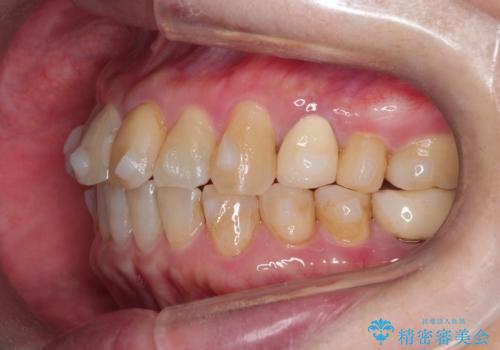

【インビザライン】前歯のガタガタを治したい

- 前歯のガタガタを主訴に来院されました。

上の歯の前突も気になってたため、奥歯の遠心移動も行いながらインビザラインにて治療を行いました。

前歯も下がり満足していただきました。

今回は奥歯の遠心移動とIPRを行って配列しています。